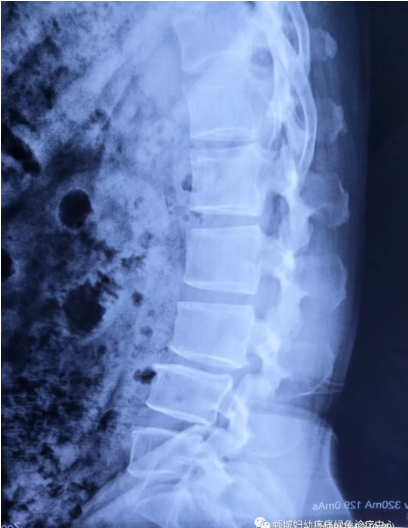

2年前,雙樓鄉(xiāng)的陳女士不小心摔了一跤后出現(xiàn)腰痛,當(dāng)時(shí)到藥店買(mǎi)了膏藥來(lái)貼,疼痛減輕了一些,但是從此以后反反復(fù)復(fù)出現(xiàn)腰痛。到處進(jìn)行治療,不見(jiàn)好轉(zhuǎn),最近腰痛加重了,痛得受不了,出現(xiàn)行走后甚至持續(xù)的雙下肢后側(cè)或后外側(cè)放射性的疼痛麻木、間歇性跛行等癥狀。陳女士趕忙去醫(yī)院治療,做了磁共振檢查后確診為腰椎滑脫、腰椎反弓。醫(yī)生都告訴她需要手術(shù)治療。隨后她又帶著片子咨詢了好幾家醫(yī)院,結(jié)果都是一樣,她已經(jīng)做好了手術(shù)的打算。

治療前

治療后